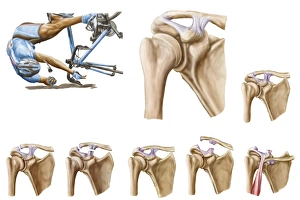

The scapula, also known as the shoulder blade, is a crucial bone in our body that plays a significant role in our mobility and stability. It forms part of the pectoral girdle and connects the upper arm to the thorax. When we examine diagrams of the bones of the hand and arm, we can see how intricately connected they are to the scapula. This connection allows us to perform various movements with precision and control. In an anterior view total shoulder joint repair image, we witness medical advancements aimed at restoring functionality to this vital joint. The intricate procedure highlights just how important it is to maintain a healthy scapula for optimal movement. Shoulder muscles artwork showcases their attachment points on the scapula, emphasizing their role in providing strength and stability during physical activities. Understanding these muscles helps us appreciate their contribution to everyday tasks like lifting or throwing. A front view of female anatomy highlighting the endocrine system reminds us that even though not directly related to the scapula, every part of our body works together harmoniously. Hormones secreted by glands within this system influence bone health and development. An anterior view of human skeletal system with labels gives us a comprehensive understanding of where exactly our scapula fits into this complex framework. It serves as an anchor point for numerous ligaments and tendons essential for proper functioning. Pictograms on an ox scapula depict ancient rituals performed to ward off danger—a testament to how cultures throughout history recognized its significance beyond mere anatomy. These artifacts remind us that humans have long understood its importance in daily life. The skeleton of an eagle after Milne-Edwards engraving demonstrates nature's adaptation at its finest—the bird's wingspan relies heavily on strong shoulder blades (scapulas) allowing it effortless flight through vast skies. Haydon's Curtius engraving captures another artistic representation showcasing human form—this time focusing on muscular structure including the scapula.